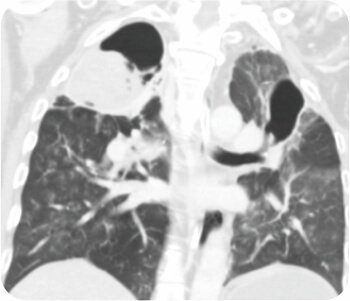

থোরাসিক এনজিওগ্রাম সহ CT বুকে হাইপারট্রফিড কোলাটারাল ধমনী সহ দ্বিপাক্ষিক গহ্বরের ক্ষত প্রকাশ করে যা প্রধানত ডান উপরের লোব গহ্বর সরবরাহ করে। FOB করা হয়েছে ডান উপরের লোব ব্রঙ্কাস থেকে সক্রিয় রক্তপাত দেখায়।

প্রাক পদ্ধতি সিটি স্ক্যান